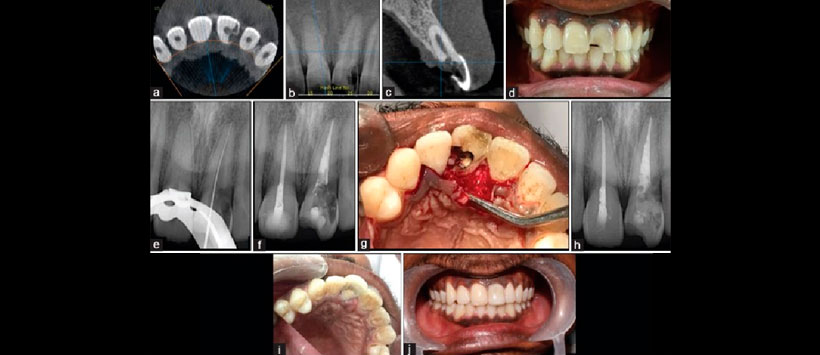

Biodentine puede demostrar ser un material particularmente adecuado para restaurar estos defectos porque puede combinar una estética aceptable con la capacidad de soportar la unión del ligamento periodontal (PDL). Los siguientes informes de casos describen el manejo quirúrgico de la resorción externa con la mejor opción de material restaurador de biodentina (ver figuras 1 y 2).

Figura 1: (a) Análisis de tomografía computarizada de haz cónico de plano axial de la reabsorción cervical invasiva en pieza 21, (b) Análisis de tomografía computarizada de haz cónico del plano coronal, (c) Análisis de tomografía computarizada de haz cónica 21 del plano sagital, (d ) fotografía intraoral preoperatoria (vista bucal), (e) determinación de la longitud de trabajo, (f) radiografía de obturación, (g) reflexión del colgajo mucoperióstico, (h) radiografía postoperatoria inmediata, (i) seguimiento postoperatorio de 6 meses (palatino vista), (j) seguimiento postoperatorio a los 6 meses (vista bucal)